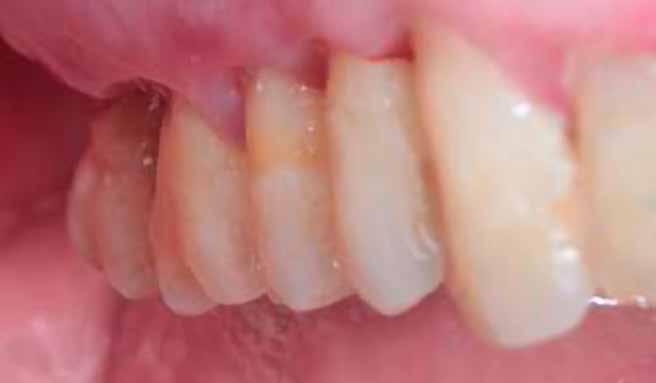

1. a–d. ábrák: Kiindulási klinikai állapot a két páciens esetében: Az első páciensnél a jobb felső premolárisok és az első moláris, a második páciensnél a bal felső második premoláris.

heléssel vagy anélkül). Az első páciensnél gyökérreszorpció miatt szükségessé vált a jobb felső premolárisok és az első moláris eltávolítása (1. a–b ábrák). A második páciensnél a bal felső második premoláris frakturát szenvedett (1. c–d ábrák) Az átfogó tervezést és diagnosztikát CBCT-felvétel segítségével végeztük (2. a–c ábrák), a posztoperatív kontroll és az utánkövetés időszakában pedig periapikális röntgenfelvételeket készítettünk. A jelen tanulmányban résztvevő valamennyi páciens nemdohányzó volt, jó, vagy gyógyszeresen jól karbantartott általános egészségi állapotnak örvendett. A hatékony plakk-kontroll ellenére műtét előtt mindkét páciensnél végeztünk supragingivális depurálást és gyökérsimítást.